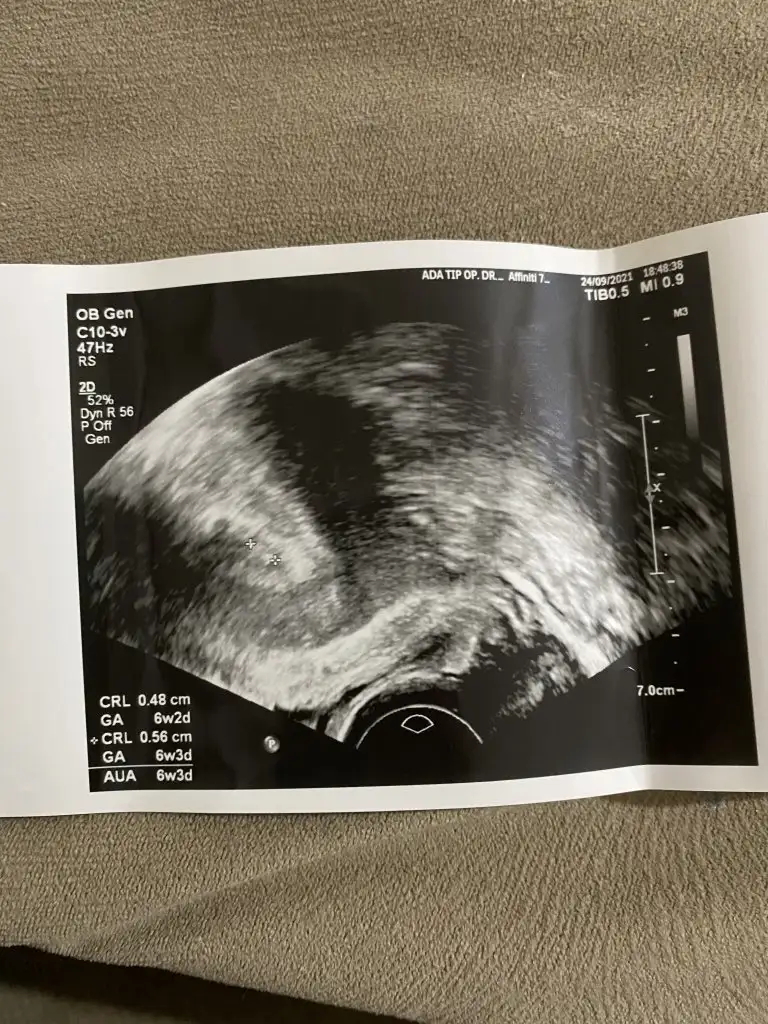

Bana da yorum yapabilir misiniz? İlk fotoğraf 6 haftalık 2 fotoğraf 9 haftalık keseye göre sizce cinsiyeti ne? :)